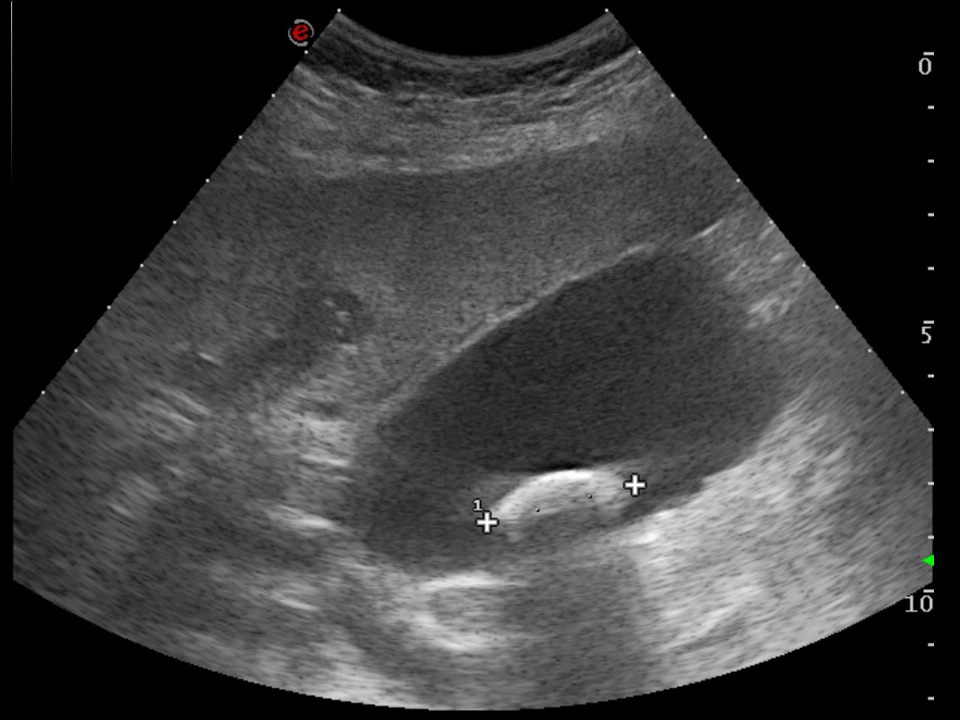

• Sometimes, the presence of a right subcostal radiopaque stone on a plain abdominal radiograph can confirm the suspicion of cholelithiasis, cholecystitis. The method of choice however, is ultrasonography. US examination can depict stones located either in the gall bladder or in the biliary tract. They are shown as hyperreflective structures with acoustic shadowing. As a sing of inflammation the bladder wall thickens, becomes multilayered and edematous. Doppler examination can reveal the consequent hypervascularization of the inflammation. When US is unable to examine the extrahepatic biliary ducts, CT will not provide additional information because the choleliths might not be radiopaque. In these cases MRCP might be indicated.

17. Typical right subcostal colic pain. Ultrasound examination. On the right is a typical picture of a cholelith with acoustic shadowing. The left image shows cholecystitis with multilayered, edematous and hypervascularized gall bladder wall. Note the intraluminal dense sludge and the presence of multiple, small gallstones.